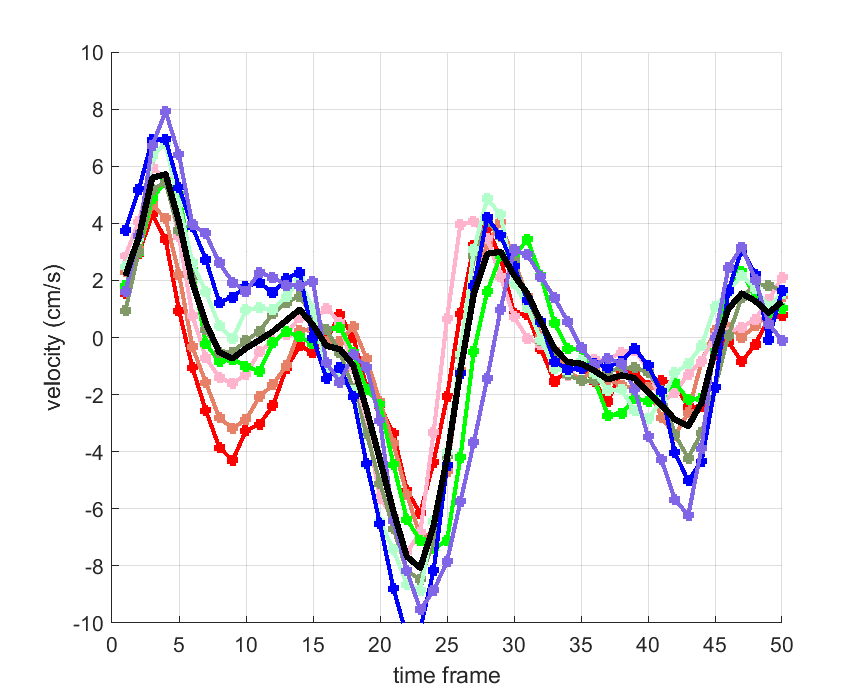

Time courses of the estimated translational component per subject, frame, slice and volume along the 3 velocity directions x, y and z are presented in Fig.6 - Fig.8.